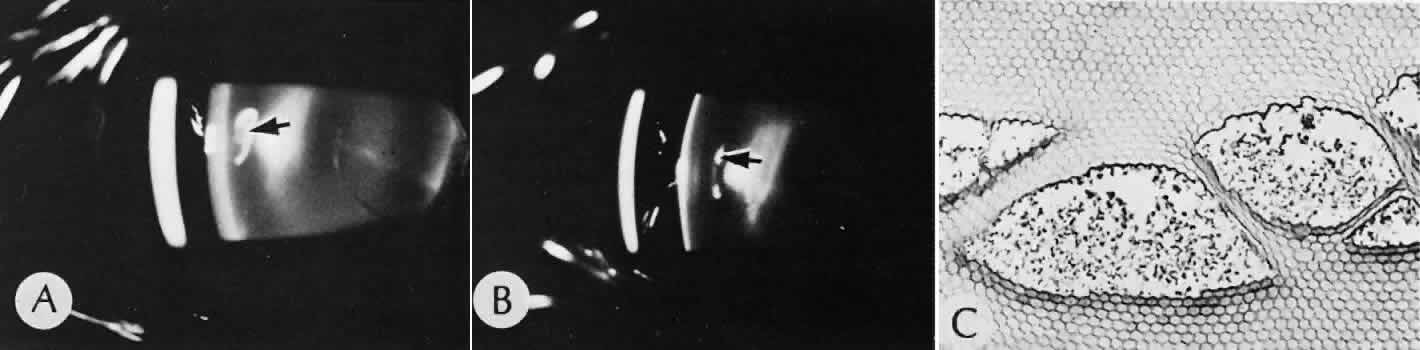

Cyclocryotherapy, cyclodiathermy (Fig. 20), and therapeutic ultrasonography apply energy directly to the pars plicata and cause lysis of the ciliary muscle and occlusion of the vascular supply, leading to extensive necrosis and scarring. Pressure lowering is accomplished by a reduction of aqueous production. Heat applied to the sclera may cause necrosis and localized scleral thinning. Cold applied to the sclera, unless extreme, does not cause any clinical or histologic changes.

Fig. 20. Cyclodiathermy treatment of the ciliary body to control glaucoma. A. Gross photograph illustrates extensive areas of depigmentation mainly in the region of the pars plana (arrows) rather than the pars plicata. B. Light micrograph of the region of the pars plana illustrates an extensive area of tissue degeneration of the pars plana (between arrows) in the late postoperative course. C. Light micrograph of the destructive effects of cyclocryotherapy also in the region of the pars plana and pars plicata. The ciliary epithelium in the early postoperative period is necrotic and cystic. (Hematoxin-eosin stain; A, × 8; B, × 16.)